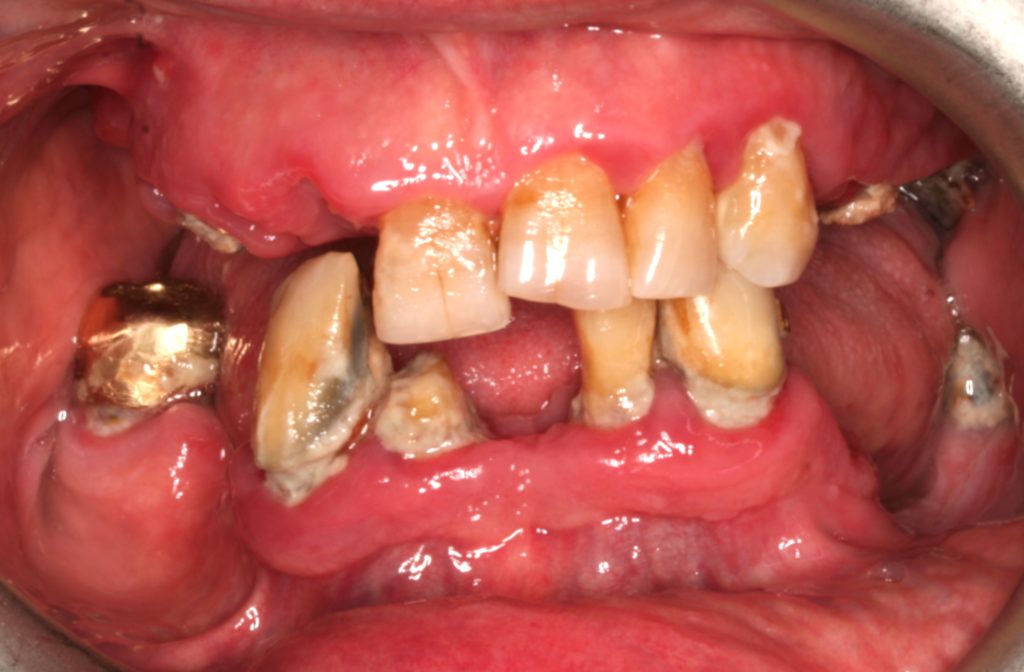

Pacjent, w wieku 74 lat, zgłosił się do leczenia protetycznego z ciężkimi zaburzeniami tkanek przyzębia, zaawansowaną próchnicą, ze szczątkowymi elementami zębów po niepowodzeniach dotychczasowych uzupełnień, z utratą wymiaru pionowego okluzji oraz ekstremalną resorpcją kości w tylnym obszarze łuku żuchwy [...]